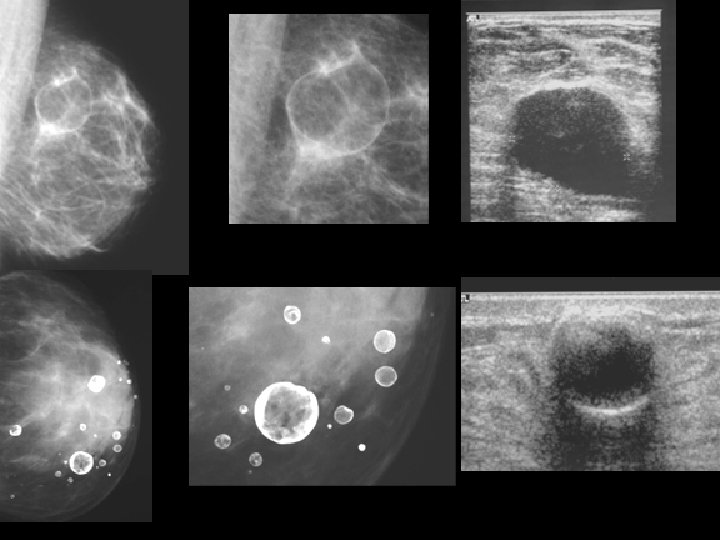

KYSTE DU SEIN • MAMMOGRAPHIE: ▫ Opacité ronde ou ovale , +/- dense, homogène, à contours réguliers (pfs polylobés). ▫ Des calcifications pariétales circonférentielles ou partielles ▫ Unique ou multiple, ▫ unilatérale ou bilatérale

KYSTE DU SEIN • ECHOGRAPHIE: examen clé ▫ Aspect typique: �lacune transonore, à limites nettes, sans ou avec paroi fine régulière. �net renforcement postérieur ▫ Aspect atypique: �liquide épais, paroi épaisse, végétations internes, cloisons �diagnostic différentiel avec : �Adénofibrome, hématome, abcès �Cancer du sein

ADENOFIBROME • MAMMOGRAPHIE: ▫ ▫ Opacité dense, ronde ou ovalaire, bien limitée Contours nets, polylobés halo radio transparent Calcifications �typiques: grossières, confluentes, (pop corn) �atypiques: punctiformes ou linéaire

ADENOFIBROME ECHOGRAPHIE: • Forme typique: ▫ Nodule ovale à grand axe transversal ▫ Contours nets et réguliers. ▫ Hypoéchogène homogène avec renforcement postérieur, cônes d’ombre latéraux ▫ Mobile et compressible sous la sonde • Les formes atypiques sont fréquentes: ▫ lésions solides ne réunissant pas tous les critères de bénignité ▫ atténuation post (composante fibreuse et/ou calcique).